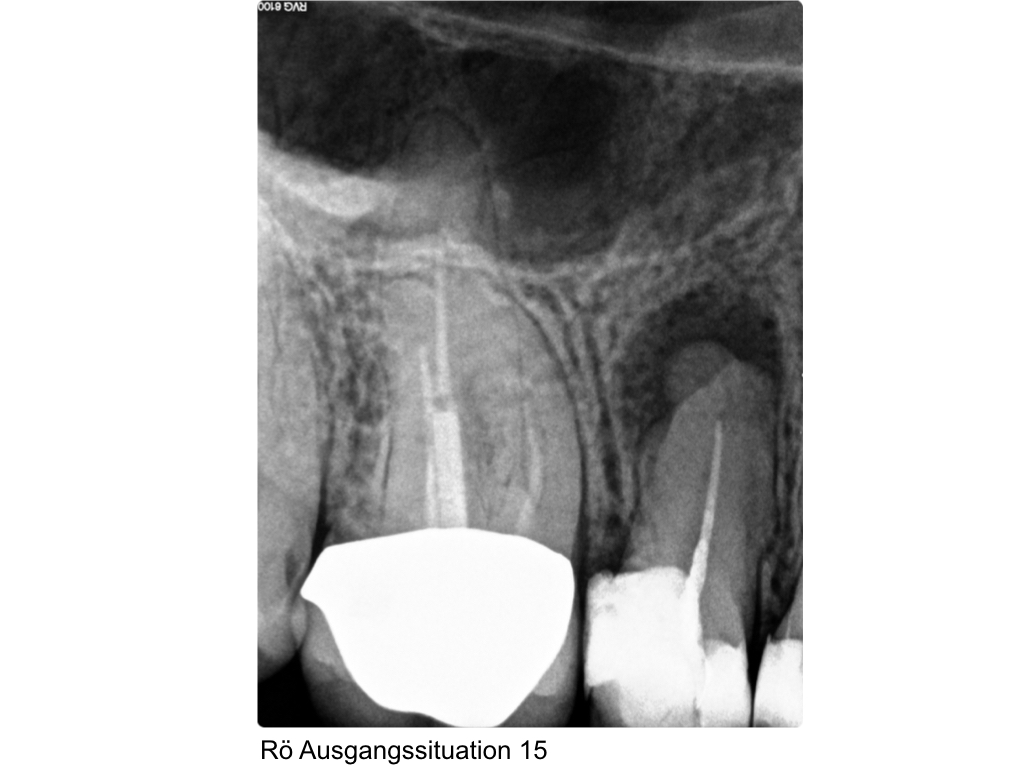

WS_Aufbau.002 Veröffentlicht 20. April 2017 am 1024 × 768 in Der präendodontische Aufbau in sequentieller Matritzentechnik